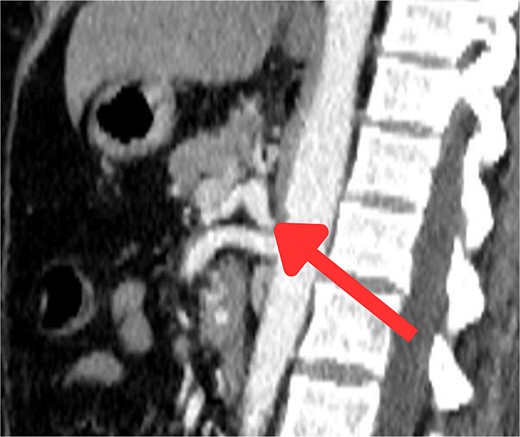

The CT scan confirmed a Dieulafoy’s lesion from the left phrenic artery (Fig. 2a and b) and showed collateral vascular channels around the pancreas with near-complete celiac trunk compression by the median arcuate ligament (Fig. 3). She underwent left phrenic artery embolization without complications, while asymptomatic celiac artery compression was treated conservatively. A follow-up endoscopy showed no bleeding or ulcers (Fig. 1d). Later, she developed severe left flank pain, and a contrast-CT revealed splenic vein thrombosis with infarction (Fig. 4), which was treated conservatively. Additionally, an incidental finding of left pleural effusion was drained. Rising inflammatory markers were managed with analgesics and IV antibiotics. She was discharged with outpatient follow-up, and at her 10-day visit, she reported improvement, stable hemoglobin, and normal inflammatory markers. She was satisfied, and a follow-up endoscopy was planned in 2 weeks.

An axial CT scan of the abdomen shows enlarged spleen with almost total liquefaction of splenic parenchyma. Findings are in keeping with splenic infarction.

In this rare case, splenic infarction occurred as a complication following the embolization of the left phrenic artery to treat a Dieulafoy lesion. While embolization is effective for controlling gastrointestinal bleeding, it carries the risk of affecting nearby organs, such as the spleen, by altering blood flow or inadvertently occluding collateral vessels, leading to ischemia and infarction. Studies report splenic infarctions in 47.3% of patients treated in the splenic hilum compared to 12.5% in those treated in the main splenic artery [9], with distal embolization causing higher infarction rates (24%) than proximal embolization (6%) [10]. Additionally, up to 37.5% of patients with splenic infarction present with left-sided pleural effusion, which can arise due to sympathetic responses [11], compression of posterior lymphatics by the enlarged spleen, or filtration of hemorrhagic splenic fluid due to perisplenic inflammation [11, 12]. In this case, the pleural effusion resulted from splenic infarction as a secondary complication following the embolization.